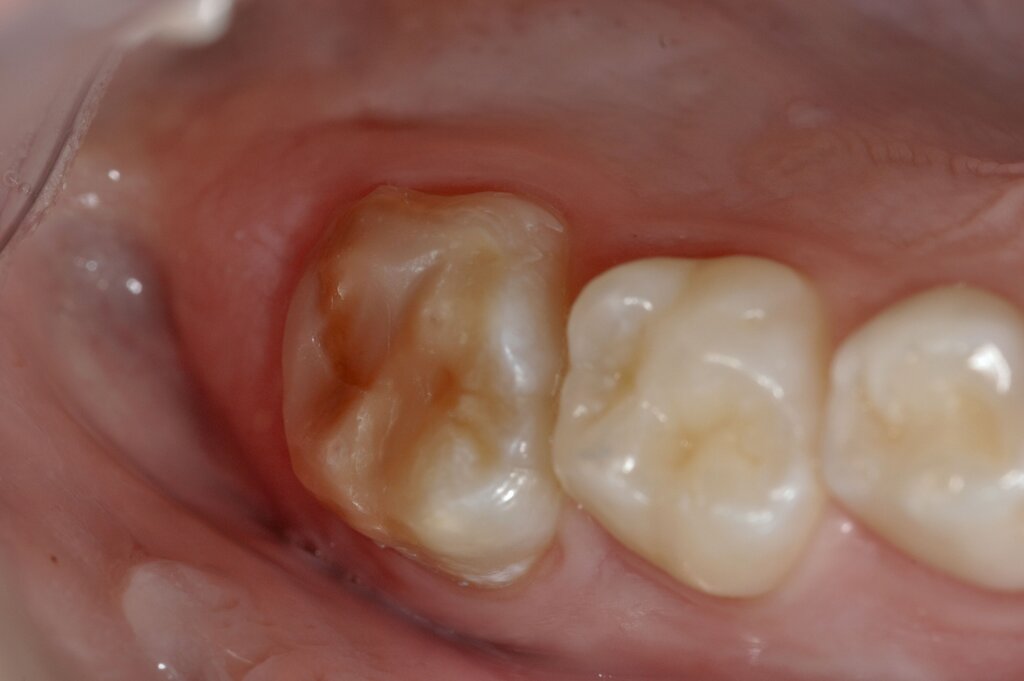

Diese Klassifikation dient als Grundlage für die Therapieempfehlungen. Deutlich wird, dass aufgrund der Symptomatik die Therapie der Zähne höchst unterschiedlich ausfällt. Dass etwa eine Opazität ohne Überempfindlichkeit (Index 1, Abbildung 1) ein anderes therapeutisches Vorgehen erfordert als ein Zahn mit nahezu komplettem Einbruch der Zahnoberfläche und mit Hypersensitivität (Index 4, Abbildung 2), ist offensichtlich.

Für die zahnärztliche Praxis gibt die Einteilung eine Orientierung darüber, welche Behandlungsmaßnahmen erforderlich sind beziehungsweise eingesetzt werden können. Je nach Schweregrad wird dabei zwischen nichtinvasiven und invasiven Maßnahmen sowie einer kurzzeitigen oder längerfristigen, restaurativen Therapie unterschieden. Bei der Überarbeitung des Konzepts wurde zudem zwischen Front- und Seitenzähnen differenziert (Abbildung 3) [Bekes et al., 2023; Steffen et al., 2017].

Für größere Defekte an MIH-Molaren müssen häufig tragende Höcker ersetzt werden. Dies stellt eine besondere Herausforderung dar, weil in diesen Fällen große Dentinflächen abgedeckt werden müssen (Abbildung 10). Da die direkte Kompositversorgung eher zur Materialermüdung und zum Verschleiß neigt, schlägt das Würzburger Konzept in diesen Fällen die indirekte adhäsive Versorgung der Zähne vor.